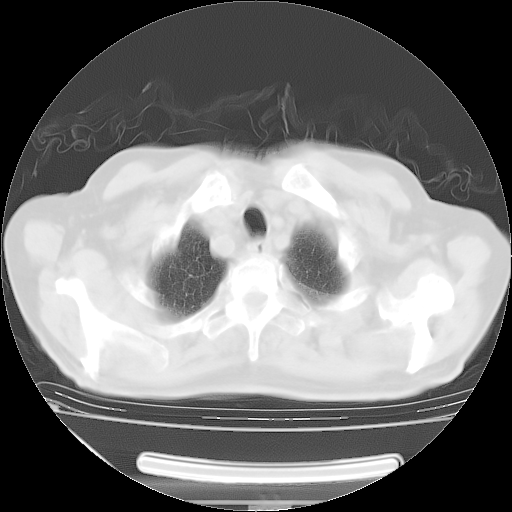

胸腹部CT,诊断意见:左上肺叶钙化灶、左侧胸膜局限性增厚并钙化、胆囊炎。描述部分肺组织呈磨玻璃样改变。